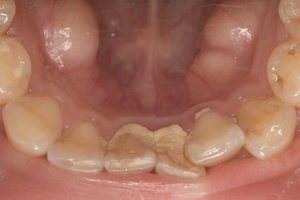

CASE 14

下顎before

下顎after

臼歯before

臼歯after

| 年齢・性別 | 27歳・男性 |

| 主訴 | 歯石とりたい |

| 治療内容 | スケーリング |

| 治療期間 | 30分 |

| 治療費 | 約1,500円(保険診療) |

| リスク・副作用 | 知覚過敏、歯肉退縮、出血 |

| 治療方針 | 歯列不正でプラークがつきやすいため、TBIを行い定期的に歯石を除去していきます。 プラークコントロールが出来るようになったら定期検診でクリーニングを行っていきます。 |